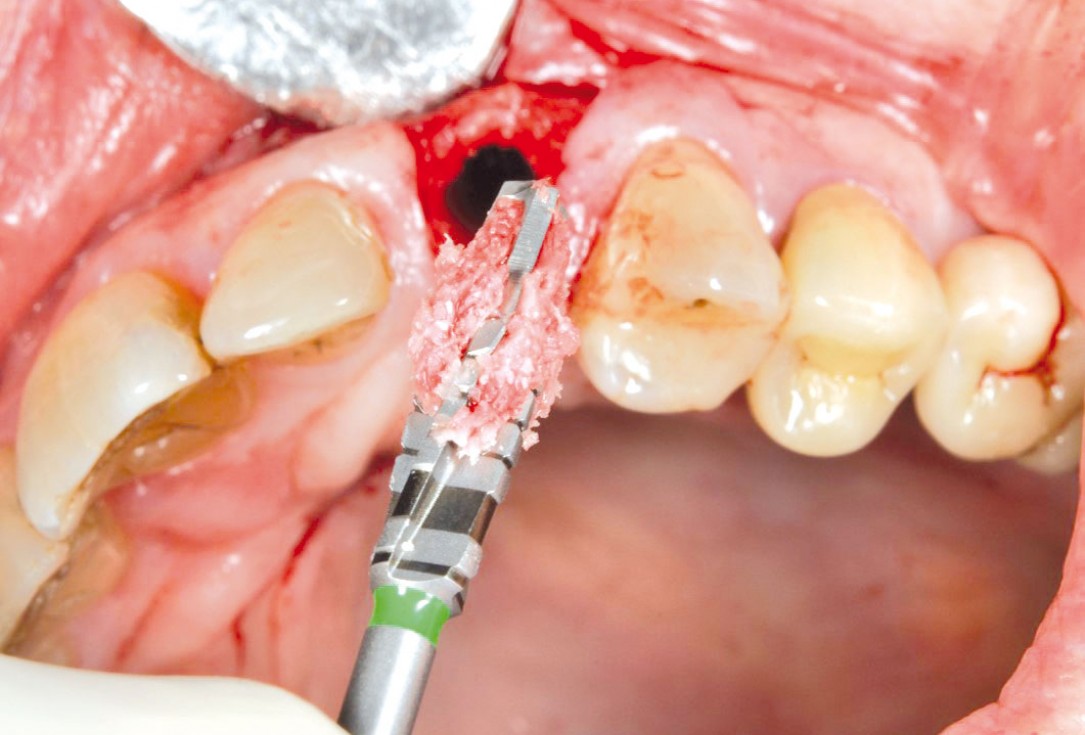

GBR with cerabone® and Jason® membrane in the front tooth region - Dr. H. Maghaireh

Initial clinical situation with gum recession and labial bone loss eight weeks following tooth extraction